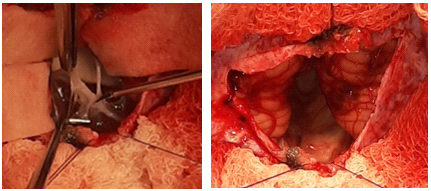

Se decidió ingresar la paciente en servicio de Neurocirugía. Teniendo en cuenta la estabilidad clínica y hemodinámica se administró acetazolamida 250 mg VO cada 8 horas. Al día siguiente fue intervenida quirúrgicamente. Se realizó un abordaje suboccipital medial mediante craneotomía osteoclásticasuboccipital bilateral (Figura 2) con paciente en decúbito prono. Se realizó una durotomía en forma de Y con electrocoagulación del seno occipital. Una vez expuesta la superficie occipital de los hemisferios cerebelosos se constató la presencia de la lesión quística en línea media, de pared delgada y transparente. (Figura 3) Se realizó la fenestración del quiste con evacuación de contenido líquido transparente e incoloro, resección parcial de sus paredes posterolaterales y comunicación con el espacio subaracnoideo. (Figura 4)

Fig.3.Durotomía en Y. Puntos de tracción dural. Superficie occipital de hemisferios cerebelosos lateralmente y quiste aracnoideo al centro.

Fig. 4.Fenestración del quiste con resección parcial de su pared posterolateral (izquierda). Cavidad luego de la resección (derecha).